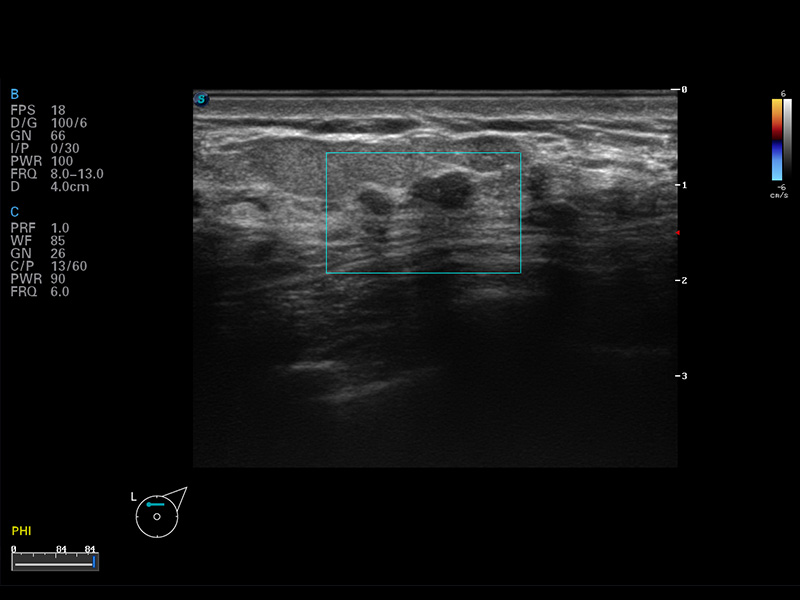

S8 EXP便携式彩色多普勒超声诊断仪是乐玩lewin国际研发的高端全身应用型便携彩超。高通道的VIS平台融合可视化(Visual)、智能化(Intelligent)和人性化(Smart)的特点,配以乐玩lewin国际自主研发生产的探头大家族,使您能够快速、准确的获得病人信息,提高工作效率的同时减轻疲劳。